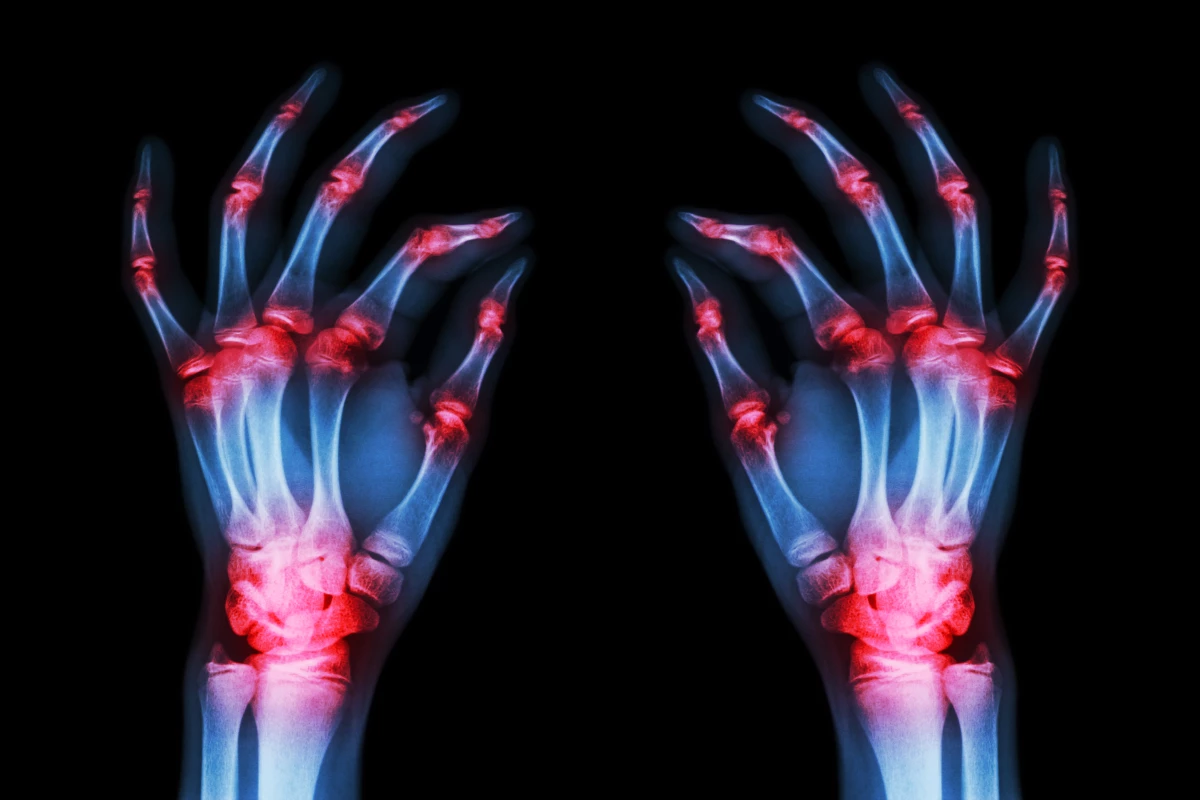

The research is still in preliminary stages but if further validated it could lead to new classes of drugs to treat rheumatoid arthritis

A team of researchers in the United States has discovered a novel mechanism in which a key protein drives the inflammatory damage associated with rheumatoid arthritis. The foundational finding is hoped to direct research toward entirely new pathways to treat this autoimmune disease affecting millions.

The new lab-based research focused on a type of human cell called synovial fibroblasts. These are the cells that line joints, and in cases of rheumatoid arthritis, inflammation in synovial fibroblasts is triggered by TNF-alpha.